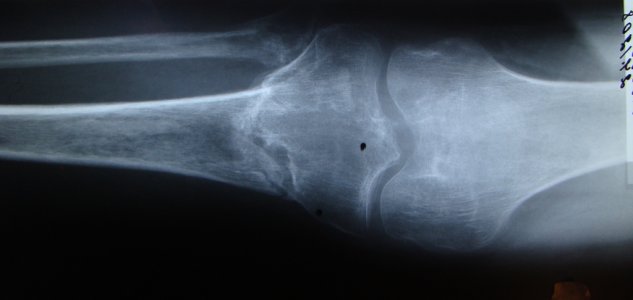

Здравствуйте доктор, 01.05.2008 года получил закрытый оскольчатый внутрисуставной чрезмыщелковый перелом костей левой голени со смещением отломков. Лечили консервативно - скелетным вытяжением. 06.06.2008 г., наложено повязку из полимерных бинтов от кончиков пальцев левой стопы до в/3 левого бедра. Проходил до 06.11.2008г. в гипсе. После было рекомендовано ходить с палочкой, Но боли не проходили и 24.12.2008 г. были сделаны дополнительные снимки из которых было видно смещение кости. Было рекомендовано, на месяц, зафиксировать ногу с помощью ортеза, что я и сделал. Доктор подскажите пожалуйста что необходимо для скорейшего срощения такого перелома (диета, припораты выробатывающие кальций?). Подскажите, глядя на последние снимки, есть ли там образование ложного сустава. Фото снимков прикреплены, название файла соответствует дате снимка. Большое спасибо, с уважением Алексей.